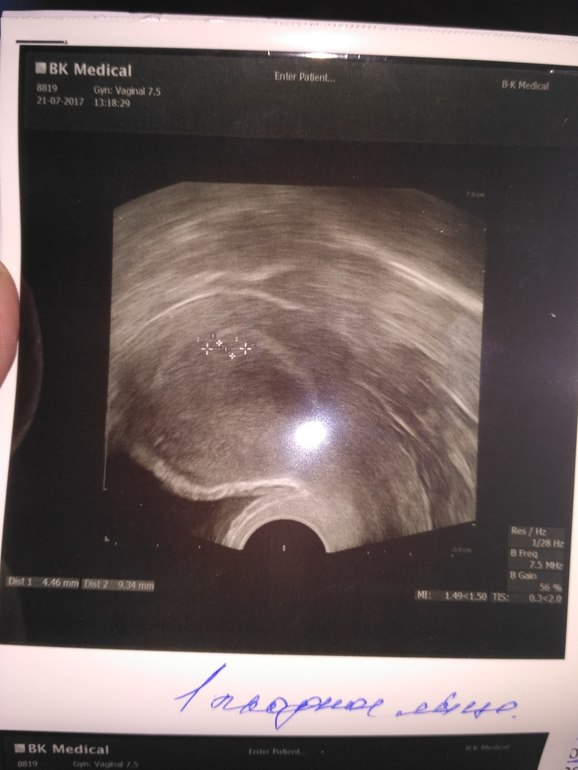

Анализы и процедуры. Помощь в расшифровке результатовВсем привет! У меня сегодня 19 ДПП, РЕ решила сделать УЗИ. Сначала водила по животику и сказала что она видит 2 ПЯ (была подсадка двух АА+АВ), куда подсаживали там и сидят, но один большой, а другой маленький (размеры не знаю). Решила сделать УЗИ вагинального, но там увидела только 1. В заключение РЕ написала одного... И сказала ждать УЗИ на СБ, возможно там появятся два сердечка... У кого такое было? Забилось два? Или одно?

у меня две двойни - и обе раза были размеры ПЯ почти в два раза меньше последняя двойня была 9.8 и 5.8 размеры , первые примрено так же и тоже думали не забьется сердечко - в итоге страшим 4 .7 гоад, младшим 7 месяцев. Ммальчик + девочка)